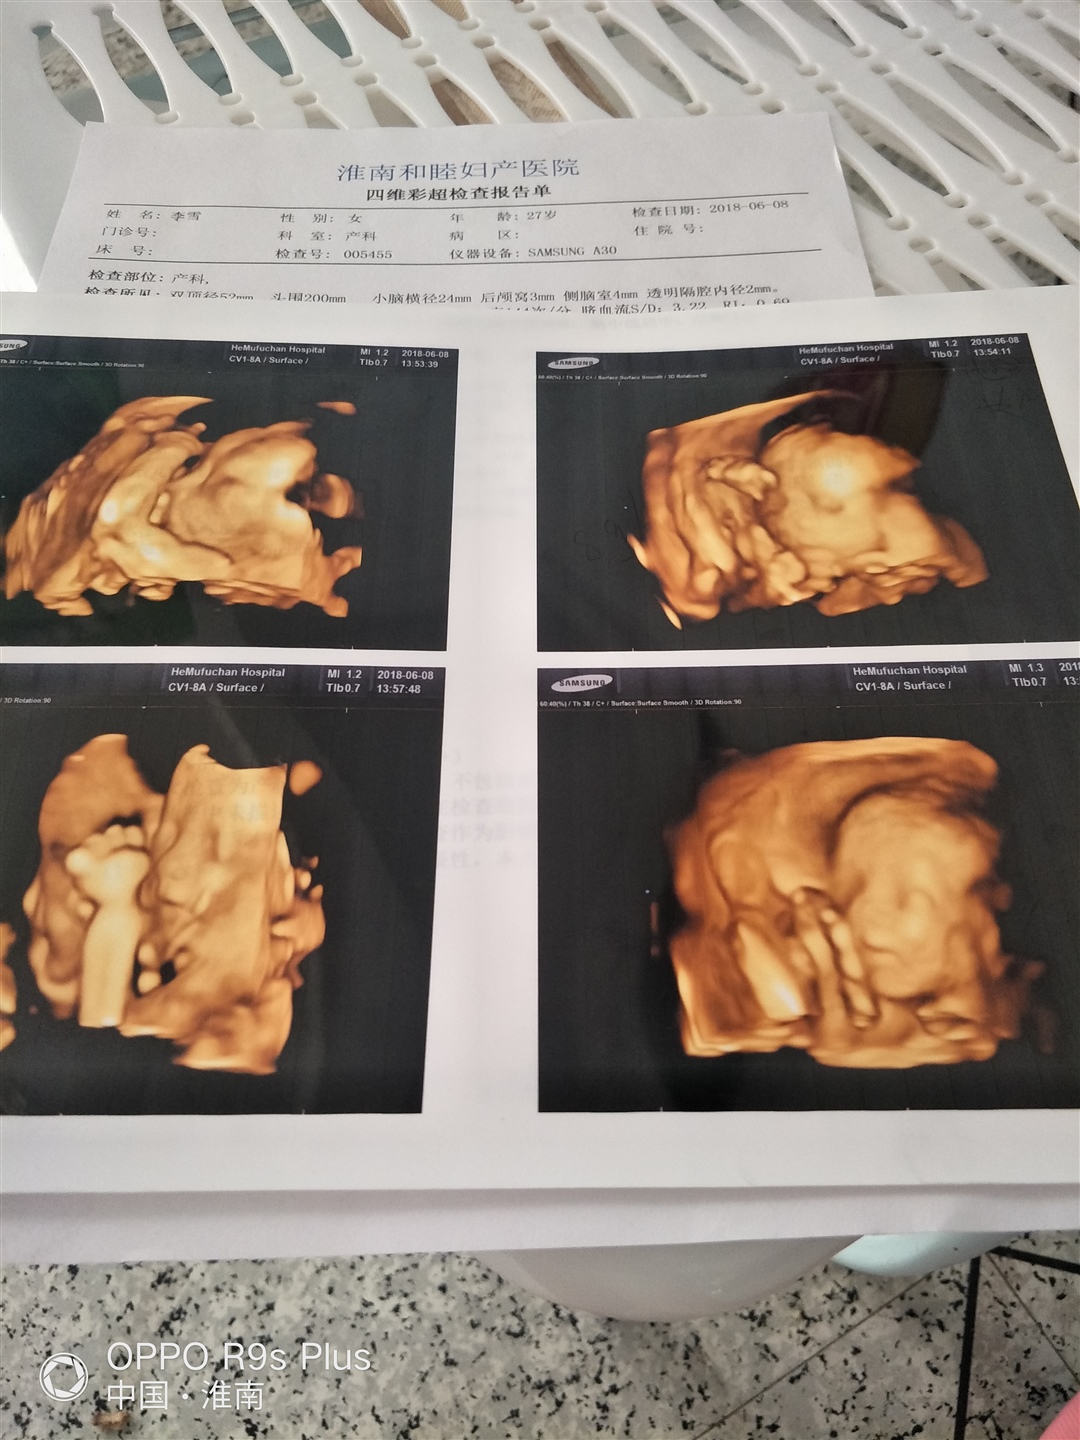

孕21周+0天

女宝吗?